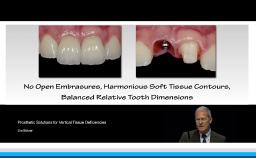

Esthetically challenging cases often involve two or more specialized clinicians working together throughout the treatment phases. This step-by-step cooperation is crucial to arriving at a pleasing esthetic result. This lecture presents various situations of compromised teeth and implants in which an interdisciplinary approach and modification are indicated. The rationale for predictable treatment and some clinical tips are also discussed.

- describe the esthetic risk factors for treatment of the anterior region

- discuss tissue modification around teeth and implants

- indicate the different uses of ceramics as final prostheses